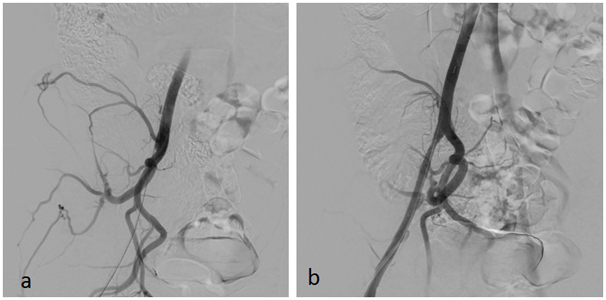

In April 2015, the patient was admitted again in our department due to the appearance in the last 24h of a short distance right lower limb claudication. In this case, the right limb presented a positive femoral pulse, but right popliteal and distal pulses were absent. Left lower limb evaluation was completely normal. The patient confirmed he kept on training and participating in elite triathlon competitions despite our recommendations. Angio CT scan confirmed a new thrombosis, now at the right EIA. Thrombus images and clinical acute presentation indicated there was a fresh, non-fibrotic thrombus in the occluded artery. A hybrid approach was selected. Through a surgical open femoral access, distal femoral control to prevent distal embolism and proximal thrombectomy with Fogarty catheters were performed. In control angiography a short stenosis was observed in the right EIA, requiring a pharmacologic balloon angioplasty with angiographic optimal final result (Figure 3A) (Figure 3B). He was discharged again 24h after the procedure with a normal physical evaluation and double antiaggregant were prescribed. In order to optimize medical treatment, hematologic evaluation was performed in order to evaluate any possible thrombophilic disease. All results were negative. Even though the patient had been informed that intensive sports were the aetiology of the iliac endofibrosis and the ischemic events, he did not stop training and competing. All clinical controls were normal until May 2016, when a new middle distance claudication appeared affecting the right lower limb. Image tests confirmed acute thrombosis of the right EIA, and an endoluminal thrombus aspiration and pharmacologic angioplasty of the right EIA were performed. Functional test and images confirm the resolution of the process (Figure 4). Since this procedure, patient seemed to understand and stopped intensive sport practise and remained asymptomatic in ambulatory controls. Chronic double antiaggregation was recommended. But, the athlete, searching for a diagnosis or therapeutic guidelines that better fit his sporting desires, requested an assessment from the Medical Services at the Olympic Training Center (OTC). In June 2016, in the OTC, during a cycle ergometer exercise test simulating a training session, the ischemic symptoms, right thigh pain, lack of pulse and pale foot, reappeared at the 15 minute at steady state power of 225 watts and 165 beats/min. The circulation recovered very slowly and the pulse did not appear until the 5 minutes of rest. That exercise response demonstrated to the athlete, finally, that an acute ischemic process in response to exercise exists, even while subject maintained drug therapy, previous good vascular diameter and by peripheral doppler scan ultrasound, without changes after short and maximal isometric contraction.